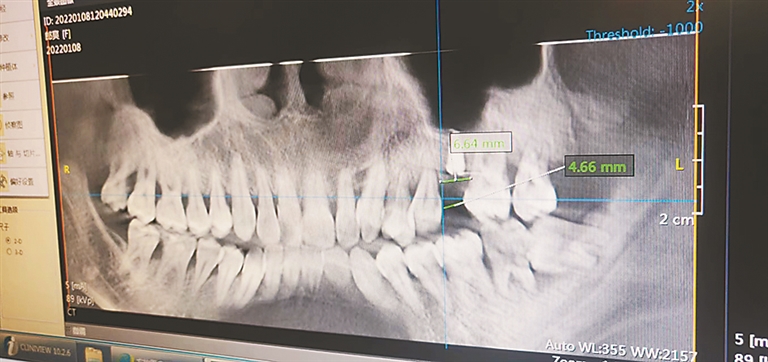

圆圈内为松动的两颗牙

郎女士表示,自己之后去相关专业牙科医院检查过,之所以会松动,可能和种牙位置相邻的两颗牙距离太近有关,“我问过其他专业牙医,还查过相关资料,缺失牙的牙位间隙至少要达到6至7毫米,而从我的片子可以看见,间隙最小的地方还不到5毫米,我怀疑医生术前没有制定周全的诊疗方案,以至于在没有达到理想的种植状态下,强行将植体植入造成的。而且这不到5毫米的距离,还是医生将后面的牙磨薄后才达到的,要不植入植体都难。”

“但通过口腔的CT片可以看见,郎女士有牙周疾病,这两颗牙的松动是受牙周病影响所致。现在医生也不确定植入植体前那两颗牙是否松动,但植体能成功植入是不会导致牙齿松动的。”随后,许先生记下郎女士的诉求后表示:“我会向青岛总公司上报,等总公司的处理结果。”

“现在患者和医院主要纠纷在于两点,植入植体前牙齿是否松动和植入后为何松动。从病人的病历来看,植入植体前没有发现牙齿松动的记录,而植入后牙齿出现了松动,这个从CT片子上看可能和牙间隙过窄以及牙周病有关,由于牙间隙过窄植入植体过程中可能会碰到相邻牙根,但正常人的话这个在植入后几个月内是可以自行恢复的,不会出现松动的问题。但郎女士有牙周疾病,一旦相邻牙根被冲击很难恢复。”该专家表示。“那么像郎女士的情况就不能种牙了吗?”“可以种牙,但要先治疗牙周病,在经过一段系统的牙周治疗后,牙周病得到一定控制的情况下才能种牙,否则确实容易出现牙齿松动的问题。”